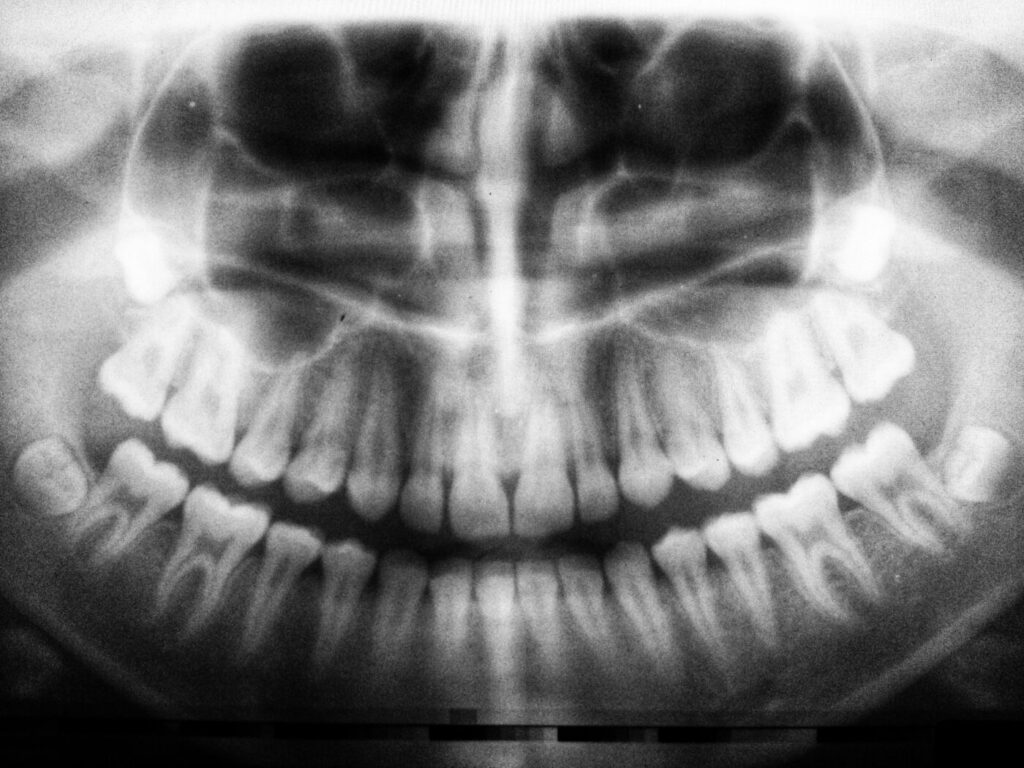

Panoramic X-ray

Very often, the dentist needs your recent panoramic x-ray to draw up a proper treatment plan or to make a correct diagnosis.

Our office is equipped with a CARESTREAM digital orthopantograph, which ensures excellent and safe imaging.